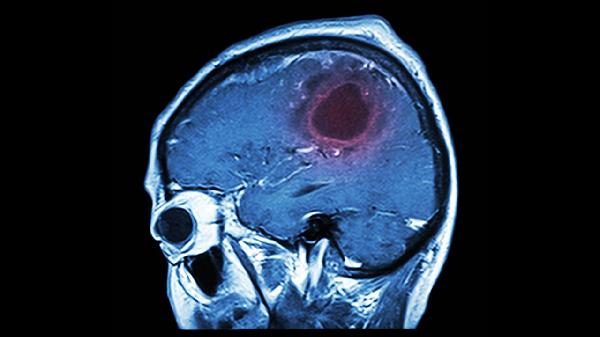

功能主治:活血化瘀,醒脑通络,潜阳熄风。用于因瘀血、肝阳上亢出现之中风先兆,如肢体麻木、头晕目眩等和脑血栓形成出现的中风不语、口眼歪斜、半身不遂等症。具有预防和治疗作用。